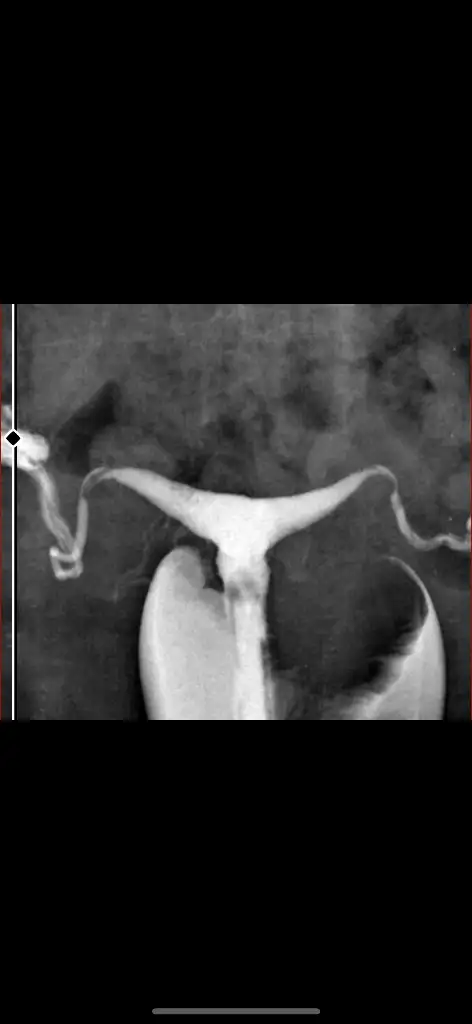

Merhaba gebeliğiniz devam ediyor mu acaba rahim şeklinizden ötürüArkadaşlar T şeklinde rahmi olup ameliyat olmadan gebe kalan ve sorunsuz doğuranlar varmı? Ben t şeklindeyim bu zamana kdr en son gittiğim doktor haricinde kimse bişey demedi. Hamileyim. Çok mu sorun yaşarım bu şekille? Hsg sonucumda t şekli izlenmiştir uterin kavite normal büyüklükte izlenmiştir yazıyor T şeklinde ama rahim yeterli büyüklükte mi demek istiyor?

evet var sizin var mı? bildirim gelmemiş yorumunuzu yeni gördümHsg görüntünüz var mı? Bana da T rahim demişlerdi, sonra başka bir doktora gittim T rahim böyle olmaz dedi, T rahim falan yokmuş yani, neredeyse ameliyat olacaktım

Merhaba bana da çeken doktor T rahim dedi kadın doğum normal dedi hsg görüntünüz nasıldı acabaHsg görüntünüz var mı? Bana da T rahim demişlerdi, sonra başka bir doktora gittim T rahim böyle olmaz dedi, T rahim falan yokmuş yani, neredeyse ameliyat olacaktım